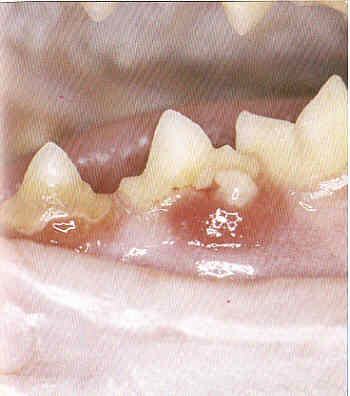

Milchzähne

Wenn Milchzähne nicht rechtzeitig ausfallen, so bildet sich mit den nachkommenden bleibenden Zähnen eine doppelte Zahnreihe. Solche Milchzähne behindern die bleibenden Zähne und müssen gezogen werden.